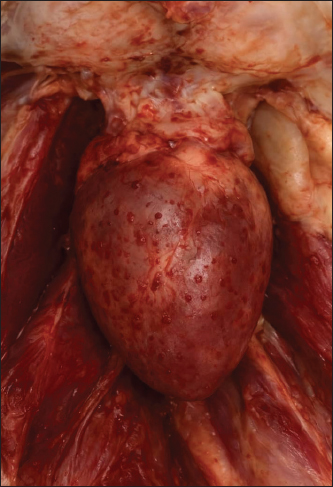

AbstractBackground: Ammonium chloride is widely used in poultry production to manage urinary and metabolic conditions; however, inappropriate dosing can lead to serious metabolic disturbances and increased mortality. This report describes a field outbreak linked to excessive ammonium chloride administration in layer chickens. Case Description: A commercial layer flock comprising 5,000 birds experienced elevated mortality, with 138 deaths (2.76%) recorded within a short period. The flock had received an estimated concentration of 5–7 g/l of a commercial ammonium chloride product (ASHIDUR) via drinking water. Clinical evaluation and laboratory findings were consistent with metabolic acidosis, evidenced by hyperchloremia, reduced bicarbonate levels, and significant elevations in hepatic and renal biochemical markers. Gross pathological examination revealed hepatomegaly, renal enlargement, visceral congestion, petechial hemorrhages, and air sacculitis. Mortality decreased markedly following corrective therapy with sodium bicarbonate. Conclusion: This case report underscores the risks associated with excessive or unsupervised use of ammonium chloride in layer chickens. Strict adherence to recommended dosing protocols and veterinary oversight is essential to prevent metabolic acidosis and associated organ damage. Keywords: Ammonium chloride, metabolic acidosis, toxicity, pathology, layers. IntroductionAmmonium chloride is widely used in poultry to acidify the system and modify electrolyte balance, especially in metabolic disorders (Olanrewaju et al., 2007; Chang et al., 2010). Excessive administration can cause severe metabolic acidosis and multi-organ dysfunction due to increased chloride ion load and bicarbonate depletion (Fudge, 2000; Ahmad et al., 2021). The clinical picture may resemble infectious diseases such as Newcastle disease and avian influenza (Alexander, 2001; Saif et al., 2008). Field cases are limited, and further reporting is essential. This case report documents clinical, pathological, and biochemical findings consistent with Ammonium chloride toxicity in layer chickens. Case DetailsA commercial flock of 5,000 layer hens (24 weeks old) experienced increased mortality after receiving an ammonium chloride–based product (ASHDUR) at an estimated dosage of 5–7 g/l for 2 days. High-dose ammonium salts disturb the acid–base balance in poultry (Khan et al., 2014 and Ahmad et al., 2021). Environmental conditions– Temperature: 22°C–24°C – Ventilation: excellent Mortality: Day 1: 11 birds Day 2: 11 birds Day 3: 25 birds Day 4: 35 birds Day 5: 56 birds Total mortality: 138 (2.76%) Clinical signs were nonspecific: depression, ruffled feathers, inappetence, and recumbency—findings typical of metabolic disturbances and toxic exposures (Al-Mayah and Al-Mayah, 2018). Gross pathological findings included the following: Intoxication with ammonium chloride can induce hepatic congestion, renal swelling, and muscular hemorrhages due to tissue acidosis (Figs. 1–4) (Farrag et al.,2015 and Abbas et al., 2017).

Fig. 3. Enlarged, dark reddish congested liver.